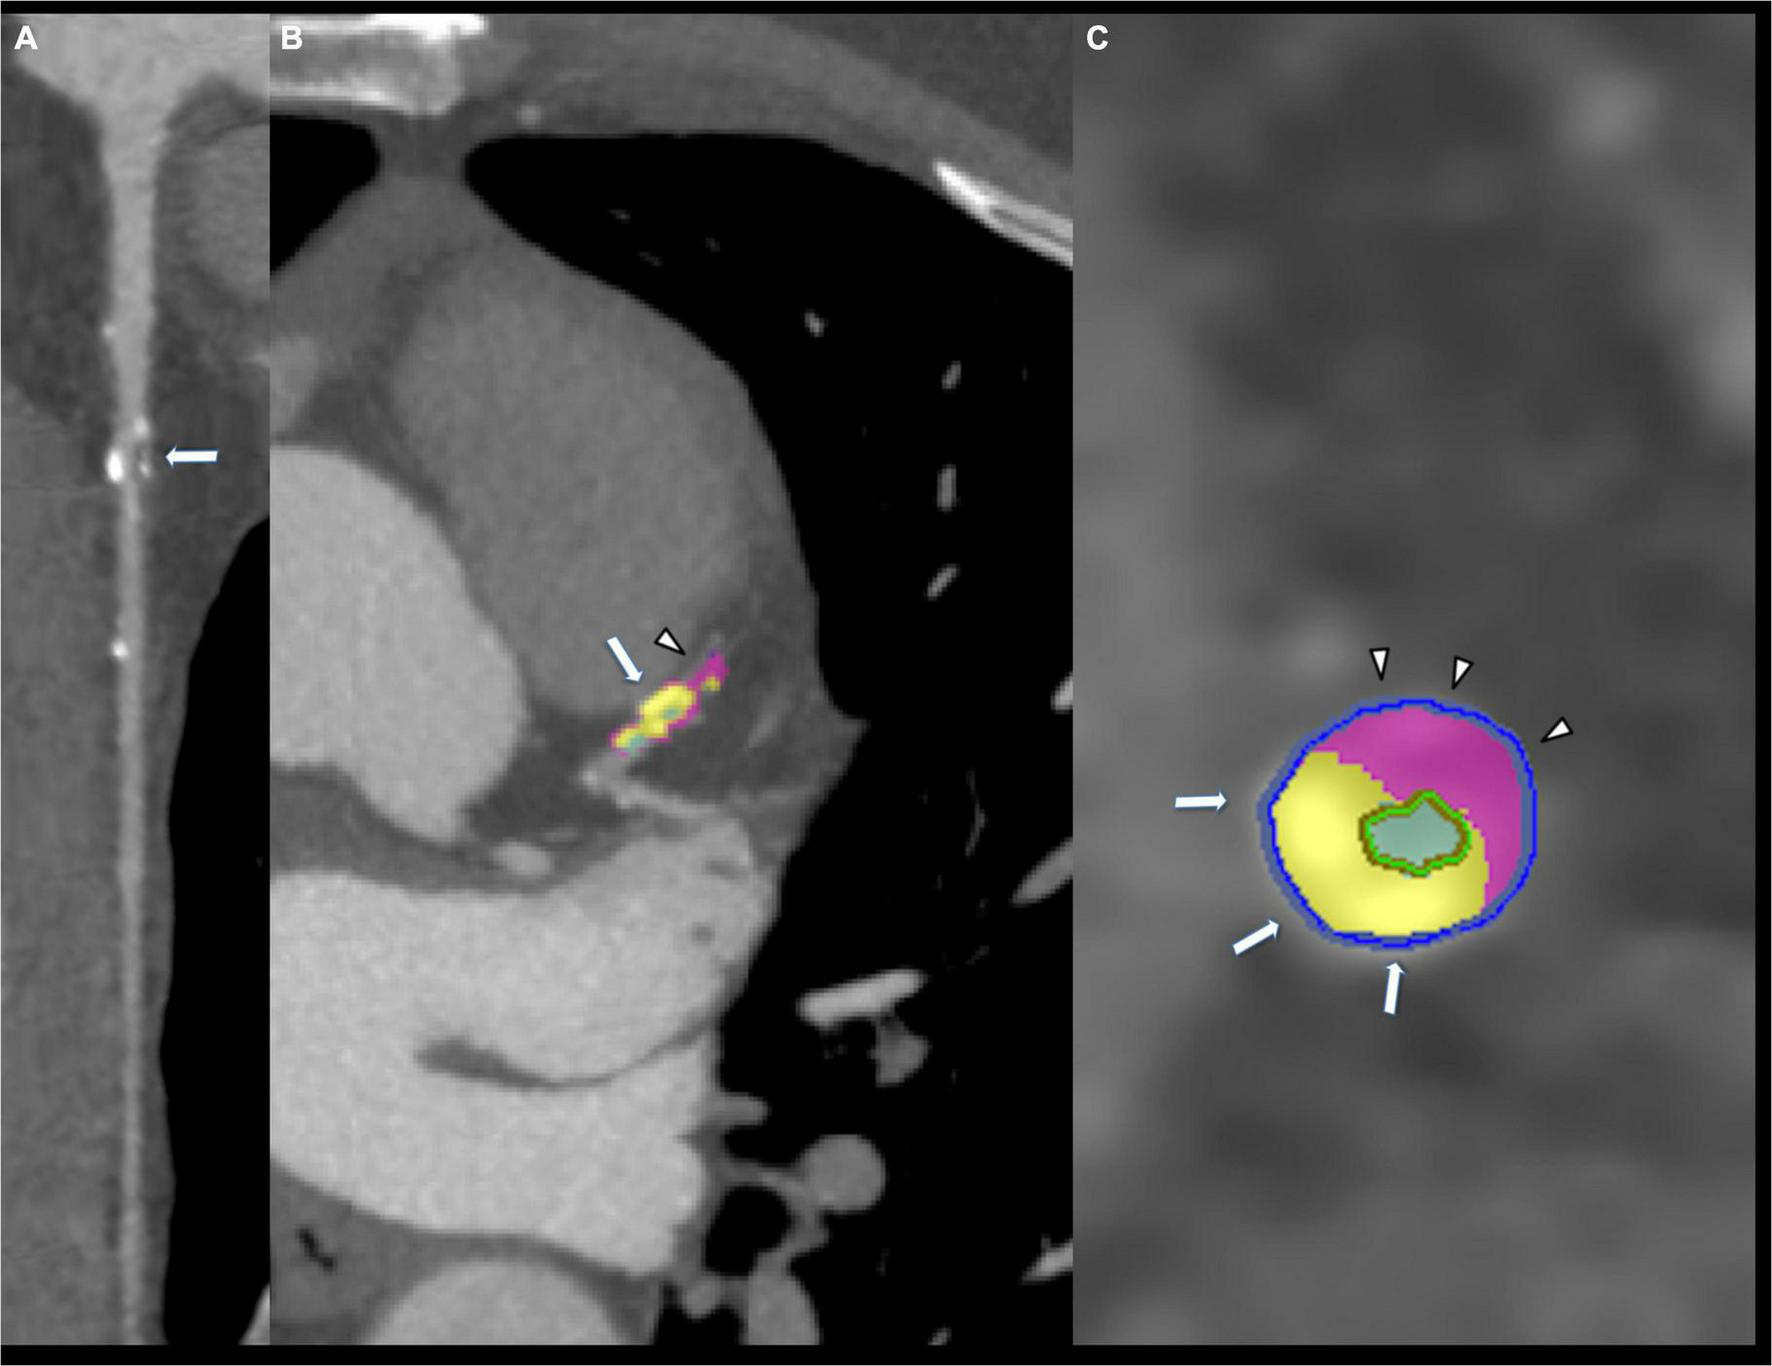

FIGURE 2

Eighty-five years old male showing mixed coronary plaque on proximal left anterior descending artery (arrow, A). Composition of plaque was composed by calcium (arrow, B,C) and fibrofatty portion (arrowhead B,C).